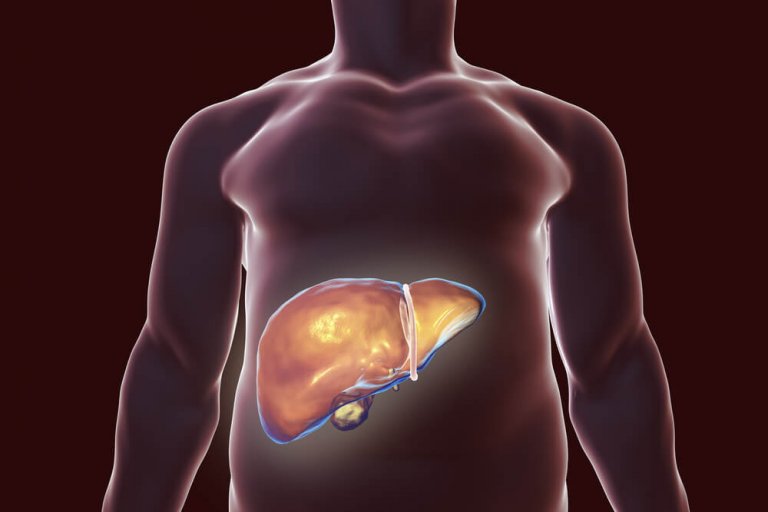

간 해독에 가장 좋은 자연 요법

이 글에서는 간 해독에 가장 좋은 자연 요법을 소개한다. 간이 제대로 기능을 하지 않으면 지방의 대사 작용이 느려져 체중을 감량하기가 어려워질 수 있다. 따라서 가능한 문제를 발견하고 간을 해독하기 위해 주의를 기울이는 것이 매우 중요하다.

간을 해독하는 것은 체내의 독소를 제거할 수 있는 유일한 방법이다.

간에 문제가 없어도 건강에 큰 이점을 제공하기 때문에 일 년에 몇 차례씩 간 해독을 할 것을 추천한다.

간에 해독이 필요하다는 몇 가지 징후는 다음과 같다.